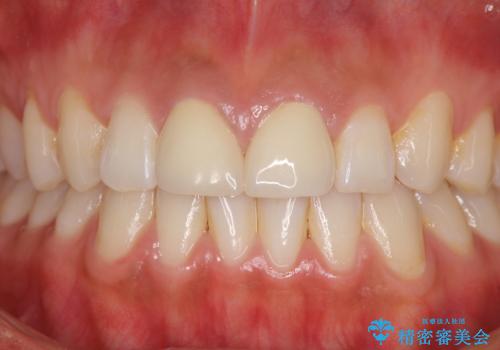

前歯の隙間をオールセラミックで閉じる

虫歯もない前歯を削ることは、処置をする者として心苦しいのですが、患者様は矯正治療は選択しないとのことだったので、オールセラミッククラウンにて補綴治療を行いました。

短期間で思い通りの仕上がりとなり、患者様には大変満足していただきました。